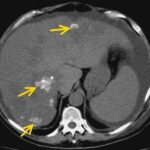

En las lesiones hipervasculares que reportamos se incluye al CHC, al hemangioma y a la HNF que fueron mejor caracterizadas en la fase arterial del estudio dinámico por TCMD. se analizaron a las lesiones hepáticas por su forma de realce en la fase arterial y reportaron un valor predictivo positivo de 82% y una especificidad de 80% en los hemangiomas, metástasis y CHC. Otros datos asociados al CHC (Anexos 8 y 9-A)(20) fueron la hepatopatía previa, fístula arterioportal y trombosis de la vena, los cuales demuestran la asociación de los CHC con fístula arterioportal, y en el seguimiento de diferentes pacientes se encontró que no necesariamente la presencia de una fístula arterioportal se asocia con tumor maligno, ya que se ha encontrado asociaciones con hemangiomas. La mayoría de las lesiones hipovasculares que se encontraron corresponden a quistes hepáticos simples. Las lesiones seudotumorales fueron representadas por los abscesos hepáticos que fueron drenados y, en segundo lugar, la infiltración grasa.

La evidencia de las lesiones hepáticas obedece tanto al número y localización dentro del hígado, como a la presencia o no de enfermedad extrahepática. Esto último es importante en el proceso de selección de aquellos pacientes a los que se les debe o no ordenar una cirugía hepática. En la tomografía sin contraste las metástasis suelen ser iso o hipodensas respecto del resto de parénquima, salvo en casos de sangrado o calcificación intralesional en que pueden ser hiperdensas. Podemos observar calcificaciones en metástasis de tumores mucinosos del tracto gastrointestinal o en metástasis de ovario, mama, pulmón, riñón y tiroides.(18) Las metástasis suelen tener el mismo comportamiento que el tumor de origen, suelen ser hipovasculares en tumores de colon, pulmón, adenocarcinoma de páncreas y en tumores de vejiga y próstata. Se observan lesiones hipervasculares en tumores primarios de tiroides, tumores neuroendócrinos (carcinoide, tumor de islotes pancreáticos, feocromocitoma) y en melanoma, cáncer renal, coriocarcinoma y sarcomas.(18-19)

Dentro de los patrones de reforzamiento de las metástasis lo más frecuente que podemos encontrar en fase arterial es la captación periférica y continua (por efecto de parasitación de la lesión y reacción desmoplástica/inflamatoria del parénquima adyacente), metástasis homogéneamente hipercaptantes (suelen ser menores de 1,5 cm), metástasis heterogéneas por fibrosis y necrosis central (> 3 cm) o con mínima captación periférica (lesiones hipovasculares).(18) En las fases portal y venosa tardía el patrón más frecuente es la captación progresiva incompleta. En menor grado se observan lesiones que se hacen isodensas con el resto de parénquima o persistencia de una mínima captación periférica (Anexo 17). El fenómeno de lavado (washout) periférico se ha descrito como hallazgo típico de metástasis, consiste en la desaparición del contraste en la periferia de la lesión en fases retardadas, es más frecuente en las metástasis hipervasculares, especialmente en tumores neuroendocrinos. Supone una mejor vascularización arterial y venosa en la periferia, donde se sitúa el tumor viable, respecto al centro de fibrosis o necrosis.(18-22)